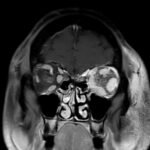

Orbital compartment syndrome (OCS) is an ophthalmologic emergency due to an acute rise in intra-orbital pressure and can result in permanent vision loss, oftentimes requiring emergent surgical decompression. Orbital compartment syndrome most commonly occurs due to recent trauma and is often easily diagnosed by history and physical exam. However, there are other causes of OCS where a more subacute/chronic rise in pressure can lead to an atypical presentation. This is a case report of a 48-year-old male who presented with left eye pain and swelling for the past 6 months. The patient had seen two ophthalmologists prior to his emergency department (ED) presentation who had prescribed him an antibiotic ointment, oral steroids, and steroid eye drops. The physical exam in the ED was concerning for increased intra-ocular pressure (IOP) and decreased vision. Ophthalmology was consulted and requested magnetic resonance angiography (MRA) to assess a vascular etiology given tortuous retinal vasculature. Emergent surgical decompression was deferred due to chronicity of symptoms, and patient was started on dorzolamide/timolol and brimonidine eye drops as well as intravenous (IV) acetazolamide with subsequent improvement in IOP. Imaging revealed a left carotid-cavernous sinus fistula (CCF), and the patient was admitted to neurosurgery. Patient successfully had an embolization with subsequent normalization of IOP and improvement of symptoms. This case is a good example of how non-traumatic causes of OCS can lead to misdiagnosis and how surgical decompression could potentially be deferred in subacute OCS.